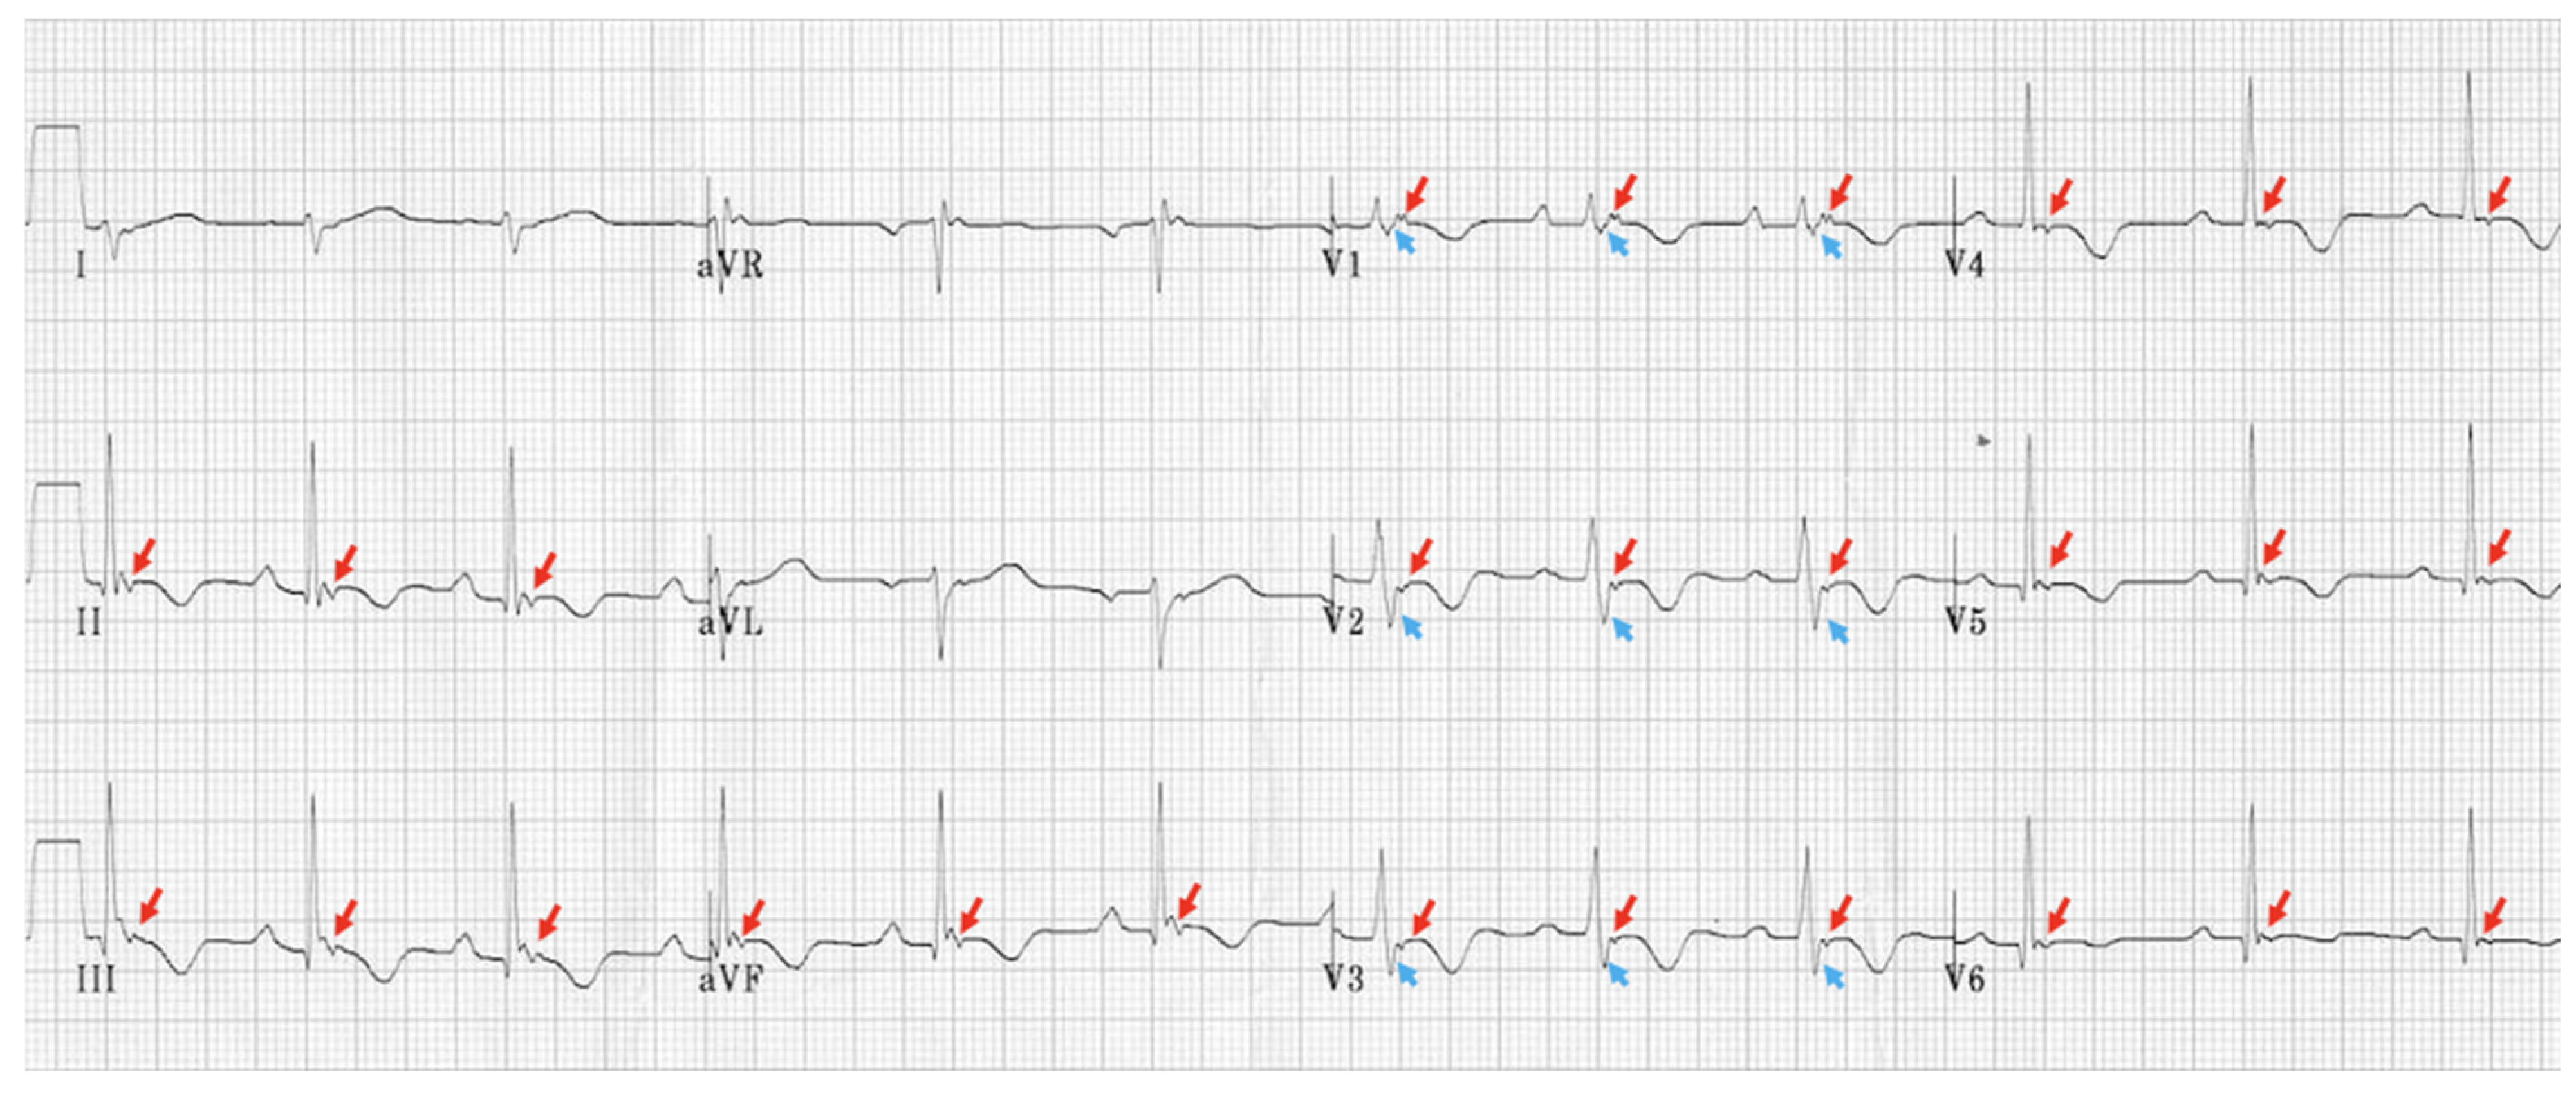

5.2.1. EKG and Holter Monitoring